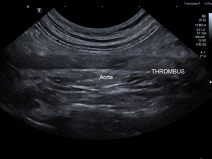

• Radiographie et échographie du thorax

La radiographie thoracique reste le premier examen complémentaire lors de l'exploration des troubles respiratoires.

L'espace d'une journée, nous vous proposons d'analyser ensemble des images radiographiques normales et anormales du chat et du chien sur des stations de travail de l'AFVAC. Seront également abordées les images échographiques normales et anormales obtenues lors de l'examen...